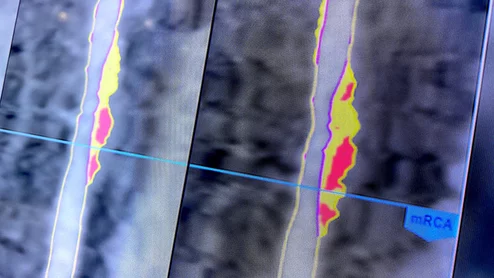

Cleerly AI plaque and coronary artery analysis at SCCT 2023. Photo by Dave Fornell

Researchers used AI-enabled software developed by Cleerly to evaluate the CCTA results of more than 6,000 patients. The software was consistently effective, identifying patients who may face an increased risk of poor outcomes.